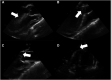

Dengue disease is found worldwide and has been spreading exponentially in the past decades. Severe forms affect about 2% of patients, sometimes leading to organ failure. Recent studies have shown that fulminant dengue myocarditis is more common than previously thought, and fatal cases have been reported. The treatment of fulminant dengue myocarditis remains supportive and is very challenging in cases of cardiogenic shock. Here, we describe four cases presenting with fulminant dengue myocarditis treated with extracorporeal membrane oxygenation, among two survived.